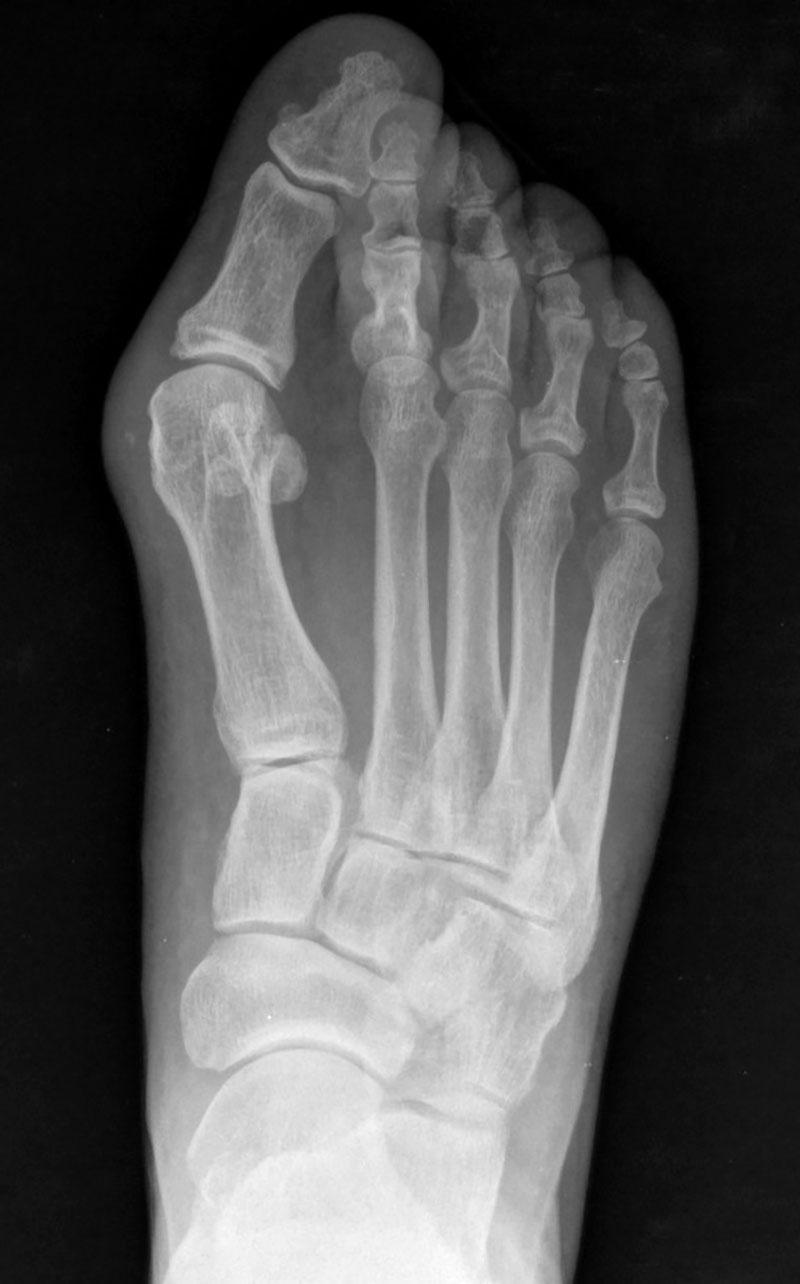

El caso que presentamos es muy representativo de la capacidad de corrección de la cirugía percutánea de tercera generación en la deformidad de Hallux Valgus. Se trata de una paciente con dolor a nivel del bunion y metatarsalgia con un 2º dedo sobre el primero que también le causa intolerancia con el calzado. Fue sometido a una técnica percutánea llamada MICA (Minimal Invasive Chevron Akin), sin ingreso y permitiendo carga inmediata

En las imágenes radiográficas se observa cómo se consigue una gran corrección en la posición de los dedos y una reducción de los sesamoideos sobre la cabeza metatarsiana. La fijación con tornillos nos va a permitir mantener esa reducción y estabilizar el montaje para reducir el dolor postoperatorio y permitir una buena consolidación ósea, como se ve en la última imagen.